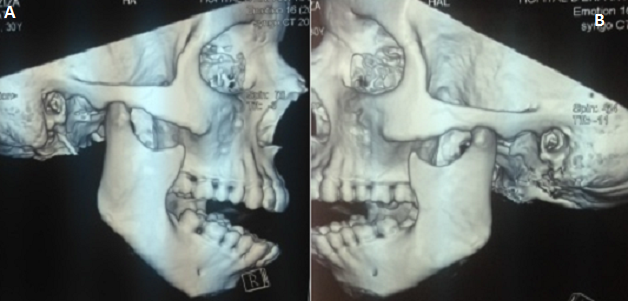

La dislocation de l'articulation temporo-mandibulaire (ATM) est définie comme la perte permanente et plus ou moins complète des relations anatomiques normales entre les condyles mandibulaires et temporales. Les facteurs de risque prédisposant à ces dislocations sont connus et comprennent des conditions telles que le dimorphisme, le syndrome de l'appareil de la mastication algo-dysfonctionnel et les antécédents de la dislocation. Ces dislocations se produisent le plus souvent après un effort de bâillement ou en cas d'ouverture forcée volontaire de la bouche. Une prédominance féminine est retrouvée dans la littérature, et serait liée, d'abord à un relâchement du ligament ordinaire en raison de l'imprégnation hormonale et d'autre part à un traitement contraceptif oestroprogestatif qui augmenterait la probabilité d'un dysfonctionnement de l'ATM. Un cas de dislocation chez une parturiente criant de douleurs lors d'un accouchement voie basse a déjà été publié dans la littérature. Nous rapportons une circonstance rare d'occurrence de cette complication: une dislocation de l'ATM lors d'une crise d'éclampsie survenant à 32 SA. Ceci a été découvert en post extubation après une prise en charge appropriée de l'éclampsie césarisée sous anesthésie générale : l'examen n'a pas révélé d'histoire passée de dislocation de l'ATM mais une ouverture bloquée de la bouche, une impossibilité d'occlusion dentaire et une vacuité des deux glénoïdes temporales sur le scanner. La dislocation a été réduite manuellement, sous sédation par le propofol. Un bandage d'immobilisation de l'articulation a été mis en place pour quelques jours avec une bonne évolution clinique et fonctionnelle.